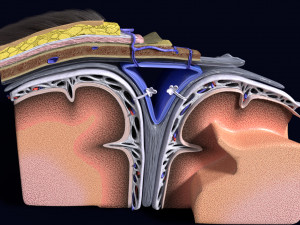

A blend model of brain along with its covering layers (meninges), skull bone and scalp labelled in detail and anatomically precise. The parts depicted are white, gray, pia, arachnoid, dura, bone, skin, fat, aponeurosis, periosteum, falx cerebri and more.